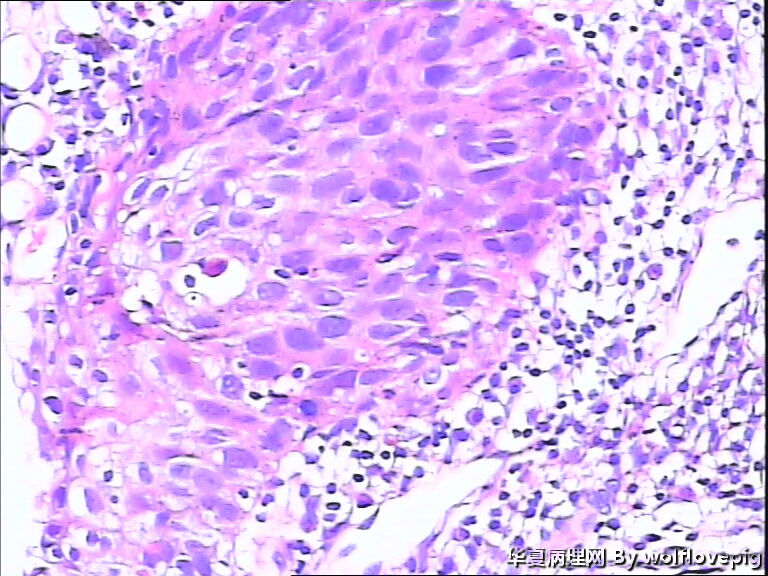

求助,宫颈!

37y

CIN II-IIl累腺

CINⅡ累腺。

CIN3累腺

CINIII累及腺体

高级别,累腺。

CINIII 累及腺体

CIN2-3,累腺

CINIII累腺。

CIN-II 累及腺体。我看不够原位癌。学习了!

同意CINIII累及腺体